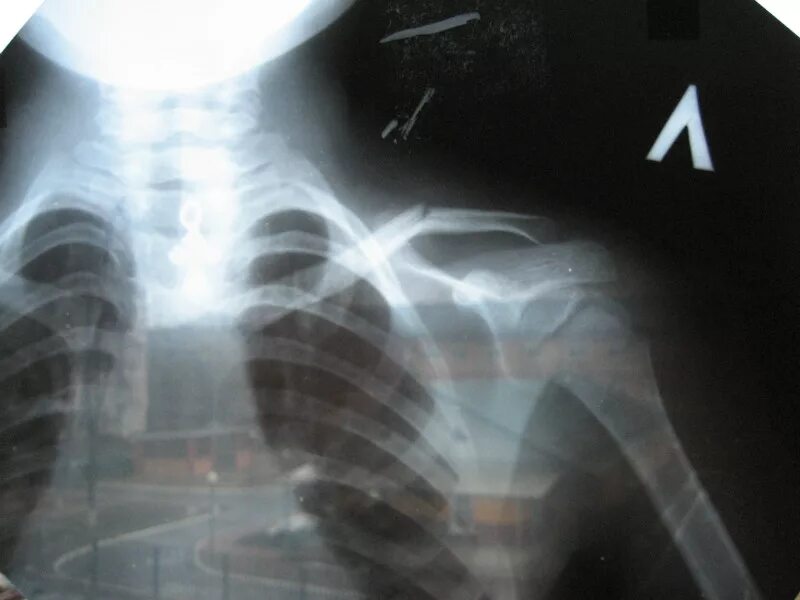

Сколько срастается ключица у детей